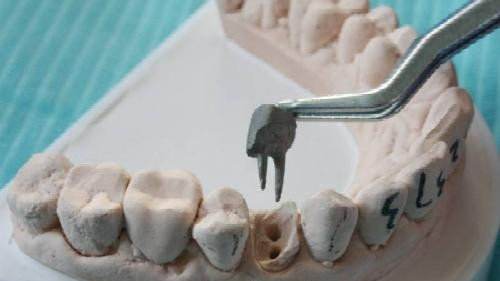

1、术前拍摄X线片:在根管治疗过程中,在根管治疗术前拍X线片,可以帮助诊断,了解髓室的位置和根管数目及形态,测量根管工作长度。

3、确定根管工作长度:应用平行投照X线方法、根管长度测量仪确定根管度,最好插针拍X片。

6、根管充填:封闭整个根管系统、堵塞主根管和侧副根管出口、防止微生物和液体的渗漏。无论是侧方加压法还是垂直加压法,应做到根管充填致密,根管充填后X线片上无根管腔隙,也不能超出根尖孔。

7、根管打桩:因牙体缺损过多,导致牙的强度(承受力量的性能)大幅度下降,不能很好地承受咀嚼力量。打桩的目的是增加牙根及牙冠的强度,增加患牙的稳固。

8、完成牙体修复:X线片显示根管充填完好,行暂时或永久牙体修复,带上牙冠,保护患牙。至此根管治疗才可算完成,同时根管治疗后还需复诊,一般周期可为3个月、半年、1年、2年或更长。